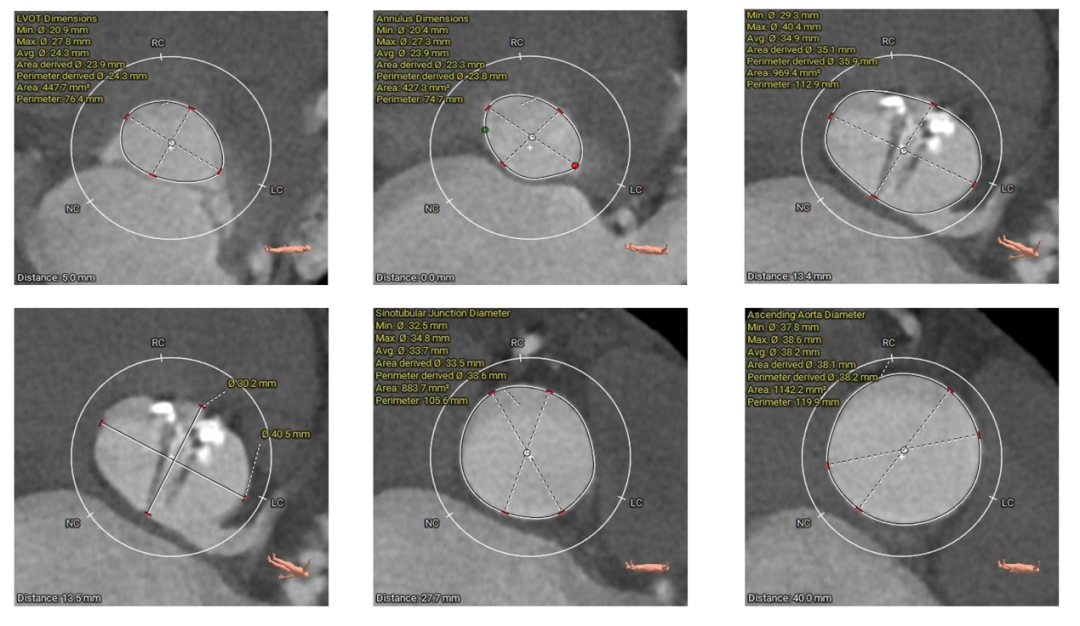

术前CT评估

主动脉根部测量

主动脉弓测量

Type-0型二叶瓣,中-重度钙化伴瓣叶增厚,左冠开口高度偏低,右冠开口高度可,左冠瓣叶长度略大于冠脉开口上缘与瓣叶附着缘距离,左室流出道整体呈直筒型,瓦氏窦,窦管交界,升主动脉内径可,左室腔内径可,心室壁增厚,主动脉瓣环与水平面夹角51度,非横位心,主动脉弓距、弓角可 -双侧入路血管走形良好,整体入路条件可

使用沛嘉20mm球囊预扩,预装沛嘉TaurusElite AV23瓣膜,释放高度瓣上0-2mm